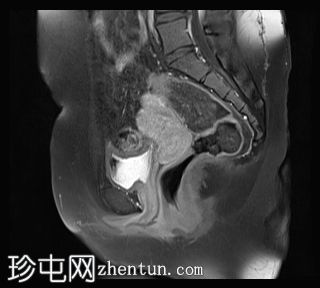

矢状位

T2加权像

右侧卵巢可见一囊肿,大小约为 2.8 × 2.0 × 2.2 cm,T1 加权像呈高信号,囊内可见液-液平面,提示囊内含有不同时期的出血性物质。由于对侧卵巢存在典型的子宫内膜异位囊肿,且该囊肿无强化,影像学表现强烈提示为另一子宫内膜异位囊肿。

子宫大小、轮廓及信号强度均正常,子宫内膜分区结构完整。未见局灶性肌层病变,子宫内膜厚度在正常范围内。

双侧卵巢囊性病变,MRI 表现符合子宫内膜异位囊肿的特征,左侧较大。未见强化壁结节或实性成分,提示无恶性转化。